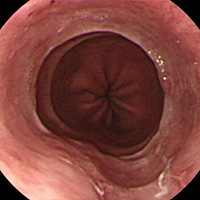

역류성 식도염

• 위식도역류질환은 '위의 내용물이 식도로 역류하여 불편한 증상이나 합병증이 발생한 경우'로 정의됩니다. 이 중 내시경 검사에서 식도 점막의 손상이 관찰되는 경우를 역류성 식도염이라고 부릅니다. 위식도역류와 관련된 증상은 있으나 내시경 검사에서 식도의 점막 손상이 관찰되지 않는 경우는 비미란성 역류질환이라고 부릅니다. 보통 가슴쓰림, 가슴의 답답함, 속쓰림, 신트림, 목에 이물질이 걸린듯한 느낌, 목 쓰림, 목소리 변화, 가슴 통증 등이 발생할 수 있습니다.